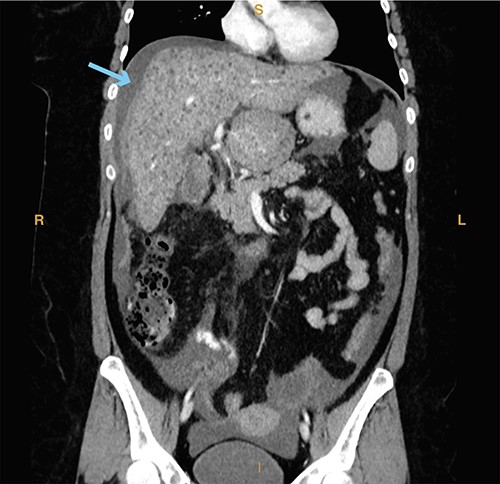

A 74-year-old man with a past medical history of type II diabetes mellitus, recent COVID-19 infection with prolonged hospital course and ventilator dependence requiring tracheostomy status post decannulation, coronary artery disease and myocardial infarction status post three-vessel coronary artery bypass graft in 1991 and drug-eluting stent placement in 2020 on dual antiplatelet therapy (DAPT; aspirin and clopidogrel) presented with acute onset epigastric and right upper quadrant pain that started 3 hours prior to presentation from a rehabilitation facility. In the emergency department, the patient was hypotensive (systolic blood pressure of 70 mmHg) with a transient response to crystalloid resuscitation. Laboratory studies revealed a hemoglobin of 8.9 g/dl, a hematocrit of 27%, leukocytosis (21.6 × 103/μl, normal range 4.3–10.8 × 103/μl), slightly elevated lactic acid to 1.9 mmol/L (normal range 0.3–1.9 mmol/l) and elevated creatinine serum to 1.43 mg/dl. Computed tomography of the abdomen and pelvis revealed a distended gallbladder containing multiple calculi and hyperdense intraluminal content (Fig. 1A). A prominent tortuous cholecystic artery branch was noted at the fundus (Fig. 1B). Hemoperitoneum with concern for acute hemorrhage was suspected, given fluid collection in the pericholecystic, perihepatic and perisplenic spaces.

(A) Computed tomography imaging from Case 1 showing a distended gallbladder with multiple calculi (cyan arrow) as well as hyperdense intraluminal fluid (magenta arrow) with collection in the pelvis (green arrow) consistent with hemorrhage. Present in the figure, the letters S, L, I and R denote superior, left, inferior and right, respectively. (B) Computed tomography imaging from Case 1 showing the tortuous path of a cholecystic artery branch (magenta arrow) at the gallbladder fundus. Present in the figure, the letters A, L, P and R denote anterior, left, posterior and right, respectively.